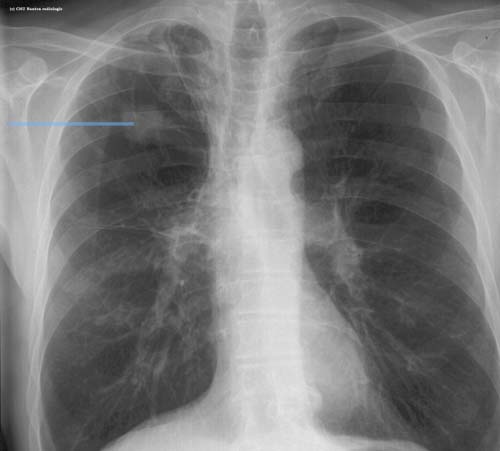

Lésion de type tumeur pulmonaire

Opacité solide aux contours spiculaires suspecte de tumeur pulmonaire primitive du lobe supérieur droit